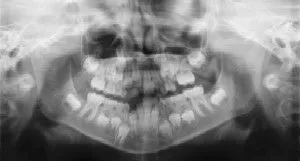

How do dental x-rays help in your child’s care?

Radiographs (X-Rays) are a vital and necessary part of your child’s dental diagnostic process. Without them, certain dental conditions can and will be missed.

Radiographs detect much more than cavities. For example, radiographs may be needed to survey erupting teeth, diagnose bone diseases, evaluate the results of an injury, or plan orthodontic treatment. Radiographs allow dentists to diagnose and treat health conditions that cannot be detected during a clinical examination. If dental problems are found and treated early, dental care is more comfortable for your child and more affordable for you.

The American Academy of Pediatric Dentistry (AAPD) recommends radiographs and examinations every six months for children with a high risk of tooth decay. On average, most pediatric dentists request radiographs approximately once a year. Approximately every 3 years, it is a good idea to obtain a complete set of radiographs, either a panoramic and bitewings or periapicals and bitewings.

Pediatric dentists are particularly careful to minimize the exposure of their patients to radiation. With contemporary safeguards, the amount of radiation received in a dental X-ray examination is extremely small. The risk is negligible. In fact, the dental radiographs represent a far smaller risk than an undetected and untreated dental problem. Lead body aprons and shields will protect your child. Today’s equipment filters out unnecessary x-rays and restricts the x-ray beam to the area of interest. High-speed film and proper shielding assure that your child receives a minimal amount of radiation exposure.